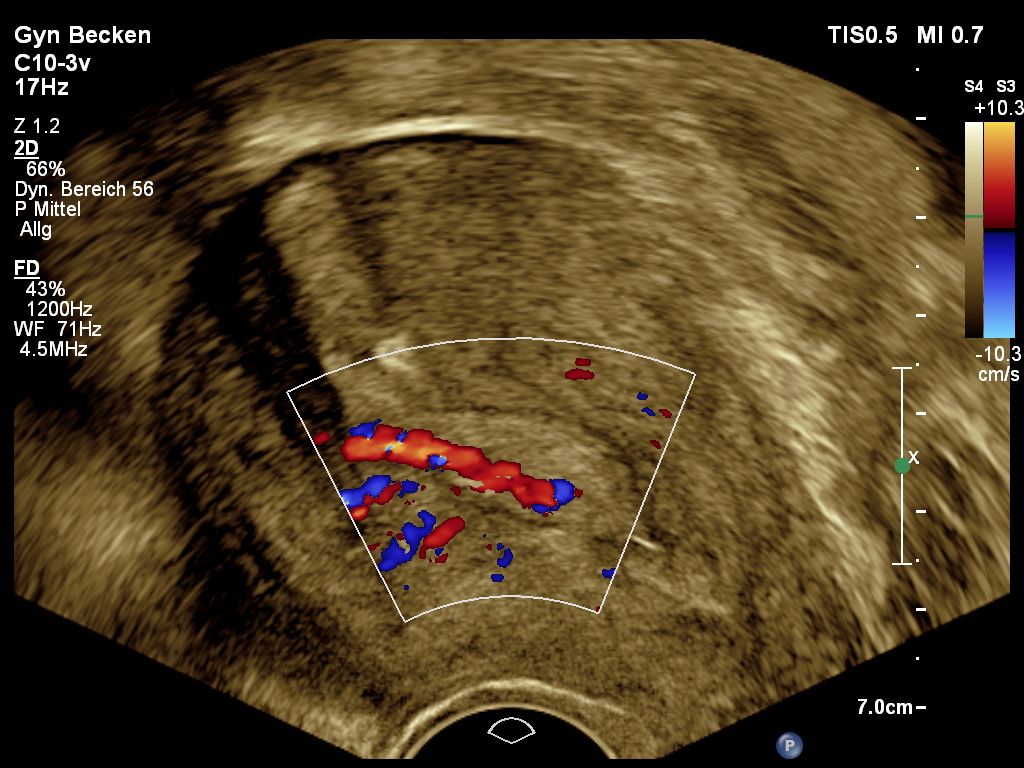

Gebärmutterpolypen Symptome, Gefahr, Behandlung VittoriaVita. Bei Polypen in der Gebärmutter kommen bildgebende Verfahren wie ein vaginaler Ultraschall oder eine Gebärmutterspiegelung infrage Polypen der Gebärmutter sind gutartige Schleimhautausstülpungen, die gehäuft in den Wechseljahren entstehen und oft symptomlos bleiben

Polyp In Der Gebärmutter. Gynäkologe Zeigt Polypen Des Endometriums Der Gebärmutter Unter Verwendung Eines Anatomischen Bei Polypen in der Gebärmutter kommen bildgebende Verfahren wie ein vaginaler Ultraschall oder eine Gebärmutterspiegelung infrage Frauen mit Polypen in der Gebärmutter haben sehr oft keine Beschwerden